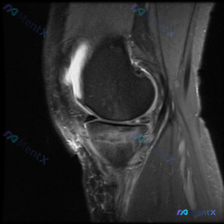

刚看到这个膝关节MRI读片的病例,有点典型,整理出来和大家分享一下思路。 病例基础信息 这是一份膝关节矢状位MRI影像,序列为T2WI或PDWI-FS,对软组织、水肿、韧带病变显示清晰。 影像学核心发现 1. 骨骼与关节软骨:髌骨后方关节软骨面不平整,髌骨软骨下骨可见片状高信号影,提示骨髓水肿或软骨...

刚看到一份膝关节MRI单矢状位切面的读片需求,核心问题是观察半月板异常,我整理了完整的分析思路分享给大家。 一、病例基本影像信息 这是一张膝关节矢状位MRI影像,根据信号特征判断:不符合典型T1加权像(骨髓信号偏低,关节软骨、积液呈高信号),更符合质子密度加权像(PDWI)或T2加权像,这类序列对半...

今天遇到一个很有代表性的情况:用户提供了一张膝关节矢状位MRI,主诉提示「半月板异常」,但我们阅片后发现结果和预期完全不一样,整理出来给大家讨论。 基本影像信息 这是一张膝关节矢状位质子密度或T2加权MRI,图像清晰度良好,信噪比适中,没有明显运动伪影,解剖结构显示清晰,层面大致位于膝关节中部区域。...